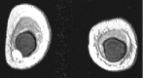

Left images show intracapsular rupture in the left implant ("linguini sign").   Right images from a contrast dynamic scan show an intensely enhancing mass adjacent to a right implant.

High-resolution MRI is extremely accurate for diagnosing silicone and saline implant rupture.   The so-called "linguini sign" refers to serpiginous thin lines seen with intracapsular rupture (left 3 images above).   Various new "silicone techniques" can also detect extracapsular extravasation of silicone.